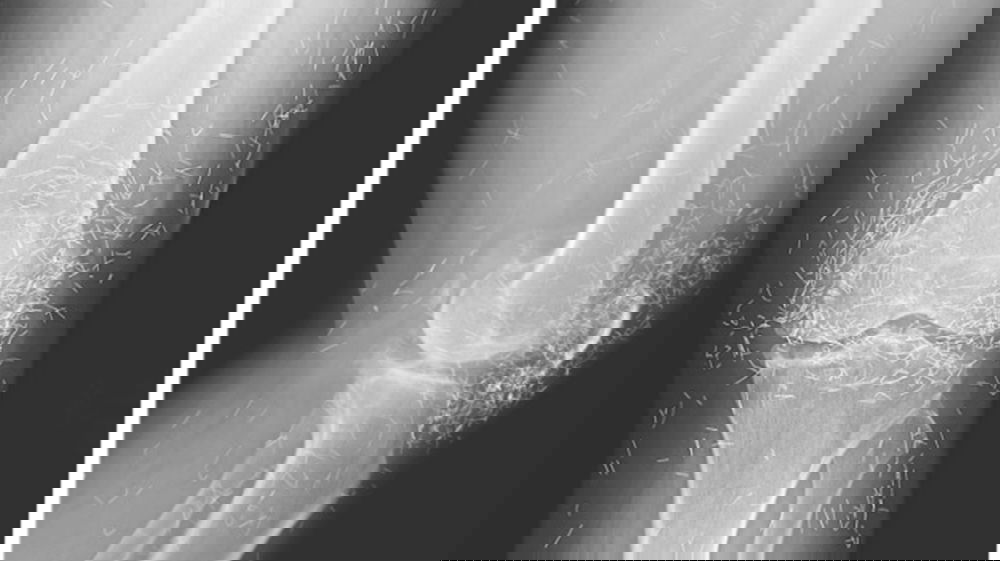

L’esame radiografico eseguito presso l’ospedale della Corea del Sud ha rivelato una realtà scioccante: le ginocchia della 65enne erano letteralmente tempestate di centinaia di minuscoli frammenti metallici.

I medici hanno identificato questi oggetti come aghi d’oro, rimasti conficcati nei tessuti per anni.Secondo quanto emerso dalle testimonianze raccolte dai sanitari, la donna si era sottoposta a una pratica nota come agopuntura permanente. In questa variante della disciplina, i piccoli strumenti non vengono estratti, ma lasciati intenzionalmente all’interno del corpo per fornire, in teoria, uno stimolo analgesico costante.

L’analisi dei medici specialisti ha evidenziato come questa scelta abbia causato l’esatto opposto del beneficio sperato. La presenza massiccia di corpi estranei ha scatenato una situazione cronica, deformando ulteriormente le articolazioni e rendendo necessaria un’azione medica complessa.La fotografia della radiografia, diventata virale sul web, serve ora da monito globale sui rischi delle pratiche mediche non convenzionali eseguite senza un rigoroso controllo scientifico. Per la paziente, la scoperta ha segnato l’inizio di un nuovo e difficile percorso di riabilitazione.